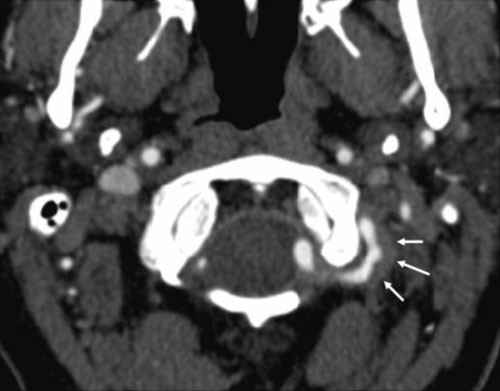

Pasienten ble utskrevet med acetylsalisylsyre og avtale om kontroll. Omtrent et år senere ble han innlagt på nytt – med akutt dysartri og uvelhet som debuterte under kiropraktorbehandling. Bildediagnostikk viste ferske infarkter i begge cerebellarhemisfærer og veggforandringer i venstre a. vertebralis, forenlig med ny disseksjon (fig 2). Kardiolog fant ikke indikasjon for transøsofageal ekkokardiografi, fordi det forelå kjent embolikilde. Det ble målt normale verdier for homocystein og protein C og S, og faktor V-/Leiden-mutasjonen ble utelukket. Man la om fra acetylsalisylsyre til klopidogrel og planla kontroll etter et halvt år.